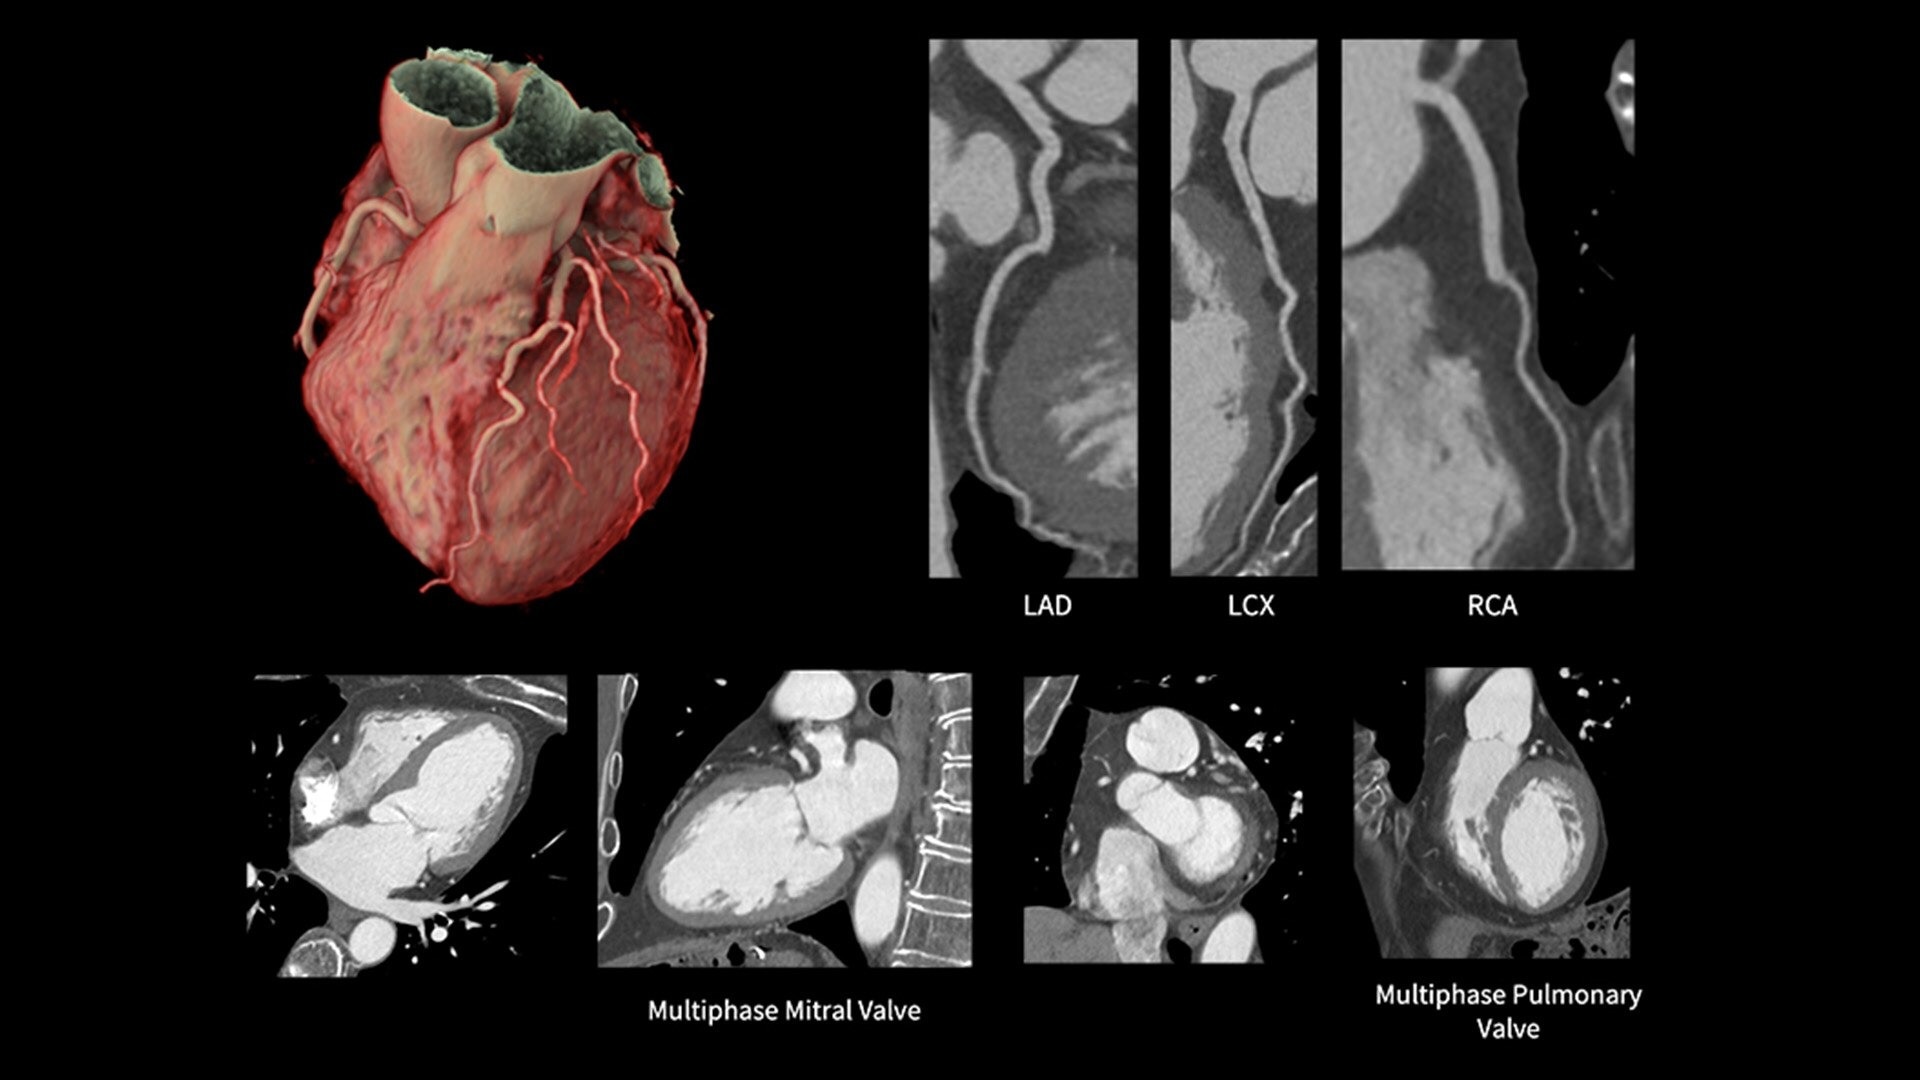

Snapshot Freeze 2 is an intelligent motion correction algorithm that's designed for coronary and valve motion correction, chambers, myocardium correction and great vessels motion correction.

ecg-less-cardiac-ct-4-ci-en